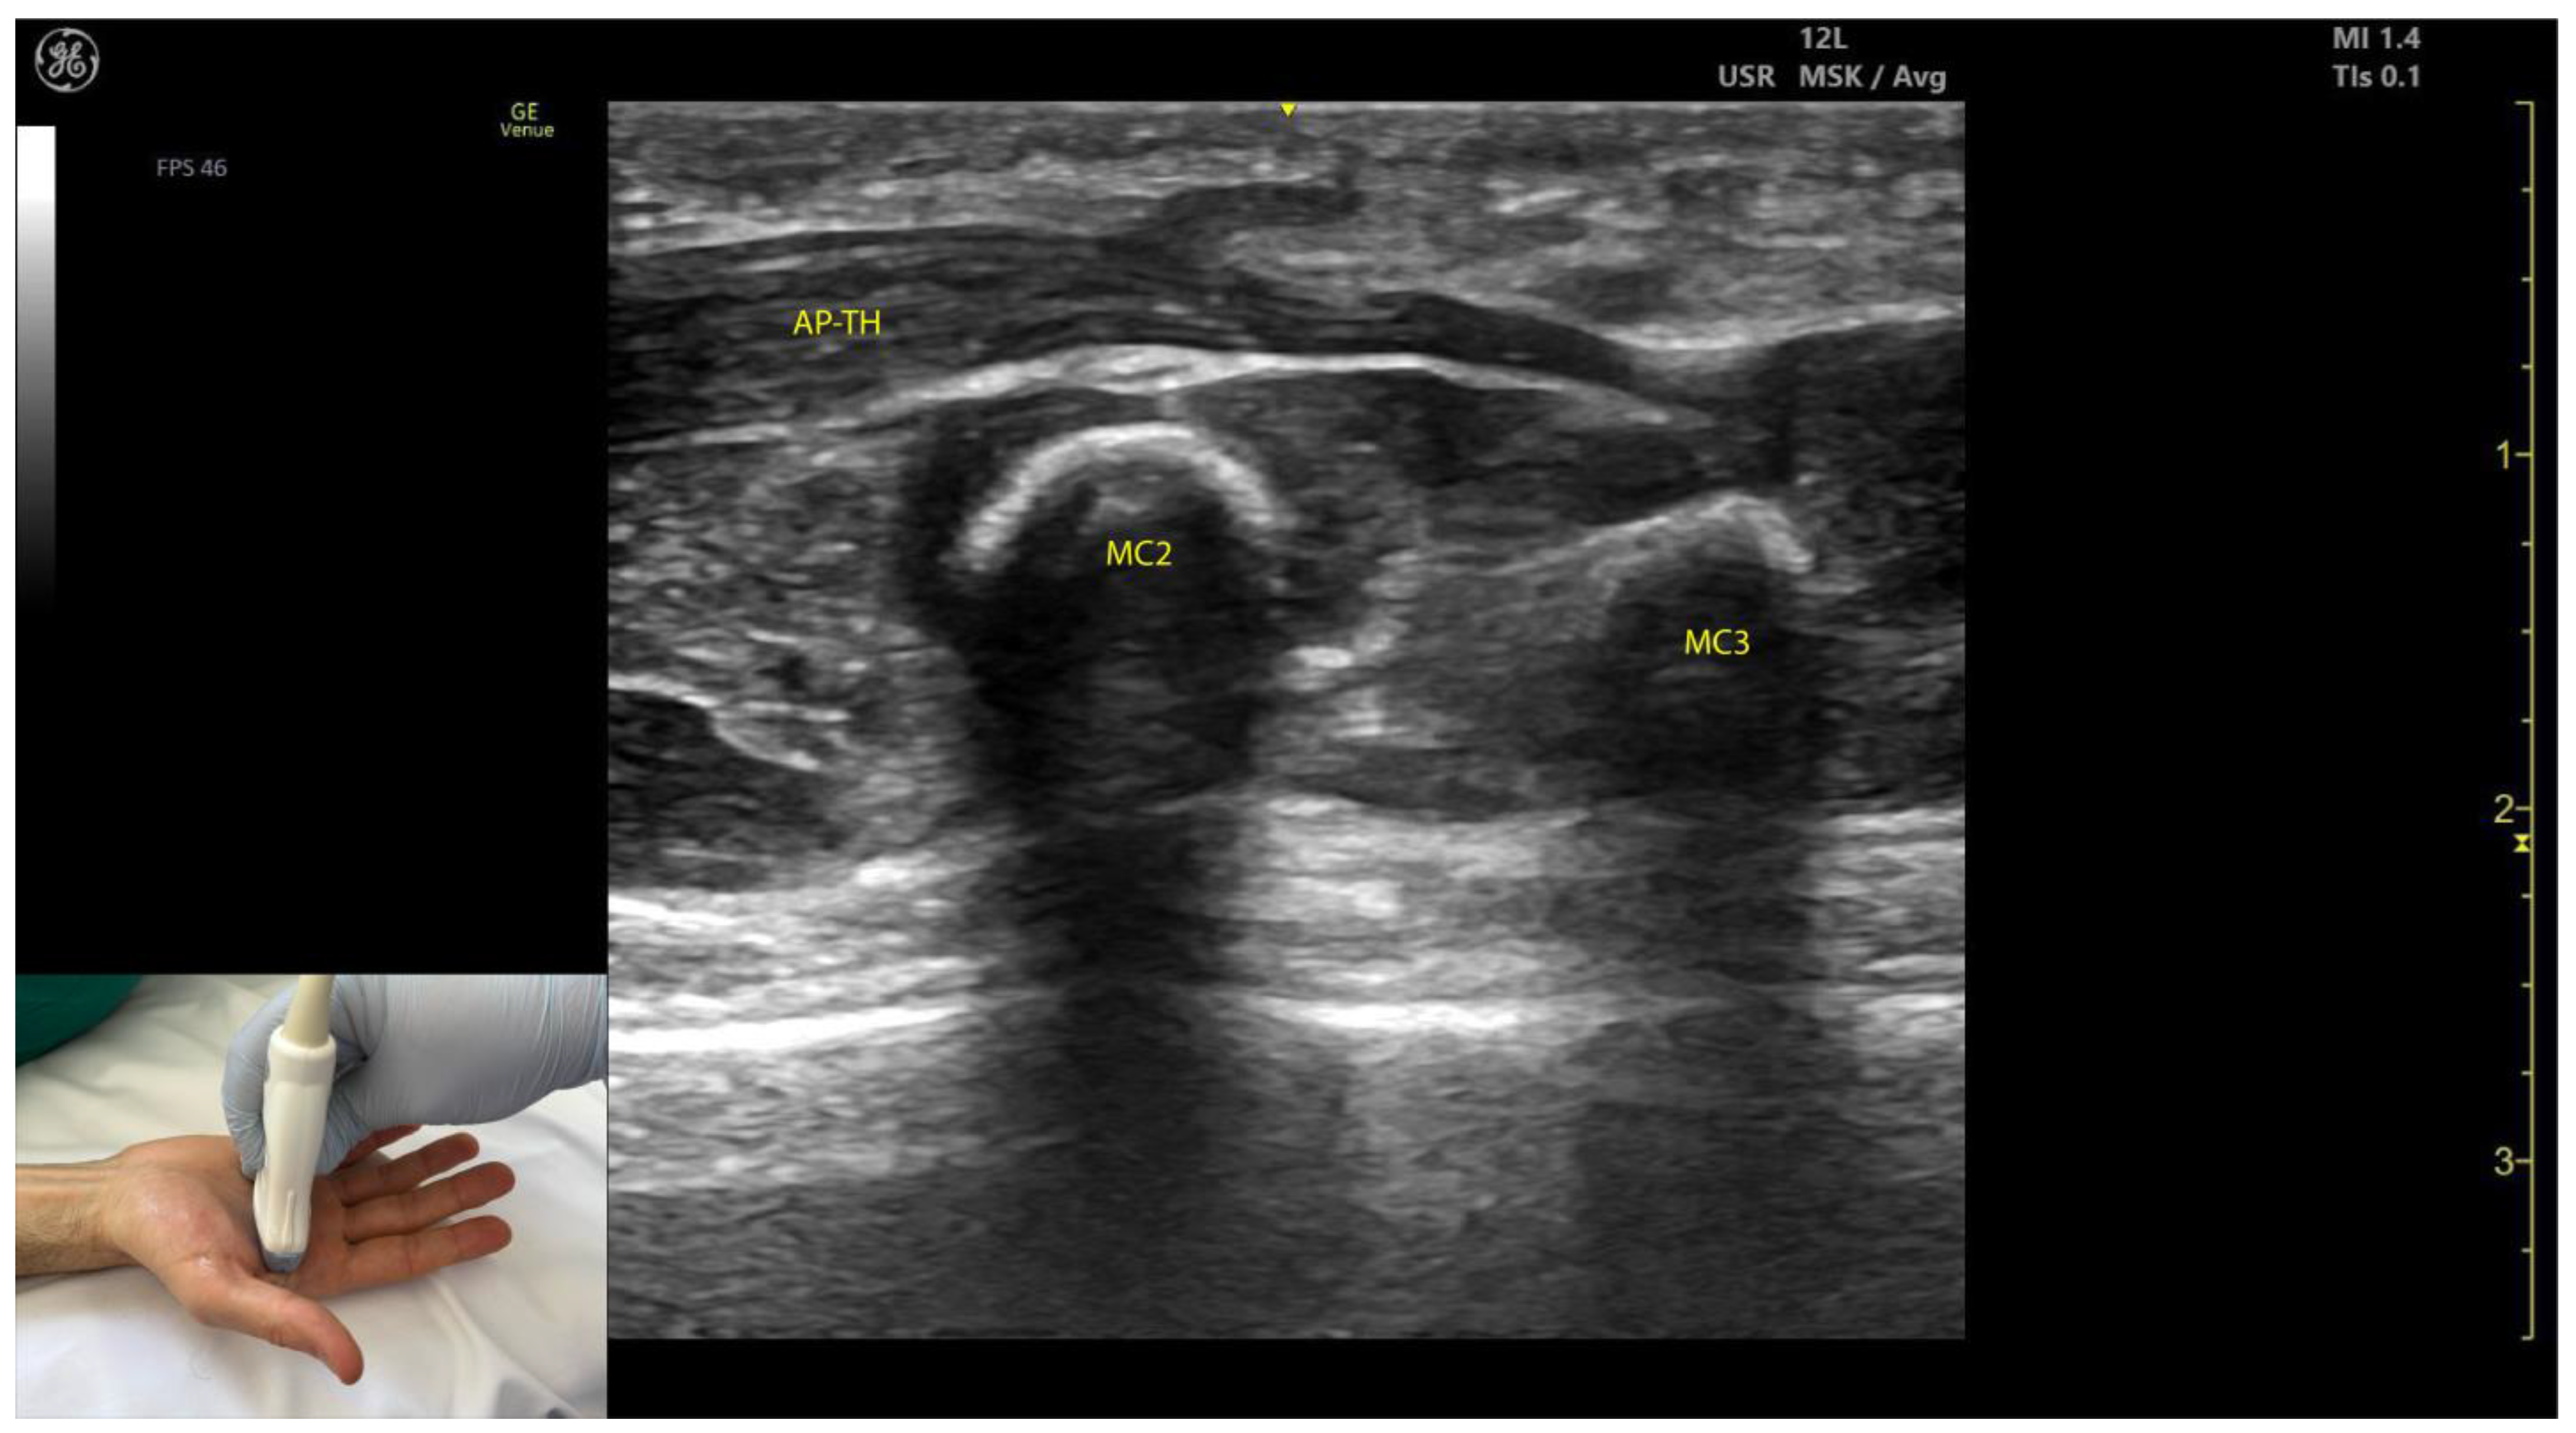

2.11.3. Key Ultrasound Landmarks (Figure 10 and Figure 11)

- Two heads: The AP consists of a transverse head and an oblique head: (i) The transverse head is identified with the transducer placed transversely on the palmar aspect at the midpoint of the second and third metacarpals. Scanning proximally (approximately 1 cm) reveals the muscle’s maximal thickness; (ii) the oblique head is visualized by angling the transducer approximately 45 degrees laterally toward the thumb. This head is located lateral to the FPL tendon and the FPB, with the first dorsal interosseous muscle in its depth [59,60];

- External fascia: The AP muscle is characterized by a pronounced fascia that clearly separates it from adjacent muscle masses, facilitating precise localization during BoNT-A injections.

- Dynamic evaluation: Contraction of the AP is observed during thumb adduction at the CMC and MCP joints or during pinch movements, such as bringing the thumb tip into contact with the index finger tip.

- In our clinical practice, BoNT-A is administered into the point of maximum muscle thickness, as determined by ultrasound. The injection is typically performed approximately 1 cm proximal to the midpoint of the second and third metacarpals, with the transducer angled 45 degrees toward the thumb to target both the transverse and oblique heads.